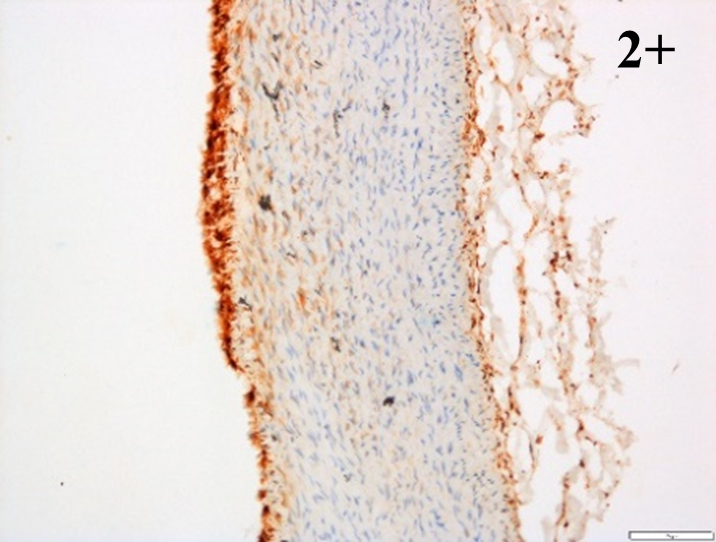

Immunoreactions of ICAM-1, VCAM-1, e-selectin, IL-6, IL-8, NF-

According to the percentage endothelial staining of cells, semi-quantitative

scores were applied. Score: 0 (negative); 1+ (1–10% positive cells); 2+

(11–25% positive cells) and 3+ (